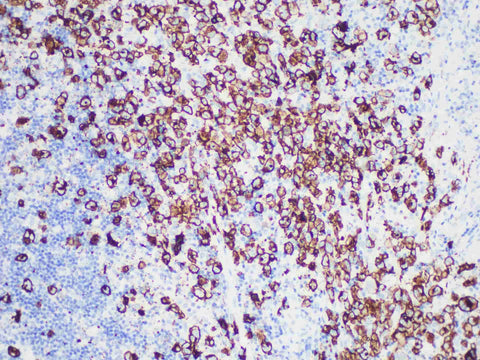

CD30 Monoclonal Antibody Stored at -20°C

Applications IHC-P

Tissue Specificity Tonsil

CD30, a member of the tumor necrosis factor receptor superfamily, is a positive regulator of apoptosis. CD30 is expressed on activated B and T lymphocytes, Hodgkin's lymphoma R-S cells, plasma cells, NK cells, monocytes, and large lymphocytes. CD30 was expressed in classical Hodgkin's disease, anaplastic large cell lymphoma and anaplastic diffuse large B-cell lymphoma. CD30 was also expressed in primary cutaneous CD30-positive lymphoproliferative disease and some mycosis fungoides. CD30 can also be used to distinguish germ cell tumors, which are positive for embryonal carcinoma but negative for seminoma.